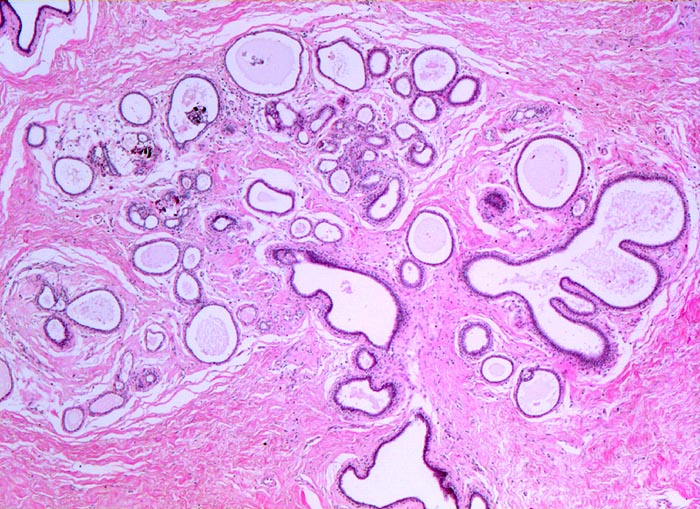

PathoPic – image database / PathoPic ID 4795 - fibrös zystische Mastopathie mit intraduktalen Mikroverkalkungen

fibrös zystische Mastopathie mit intraduktalen Mikroverkalkungen

Mammagewebe mit fibrosiertem interlobulärem Stroma. Stroma der Drüsenläppchen ebenfalls fibrosiert (verdichtetes Kollagen). Die Ausführgänge sind teilweise erweitert und enthalten teilweise Mikrokalk.

Probeexzision wegen umschriebenen Mikroverkalkungen in der Screeningmammographie. Bei der Palpation lassen sich mehrere unscharf begrenzte derbe Knoten tasten.

Histologie

320